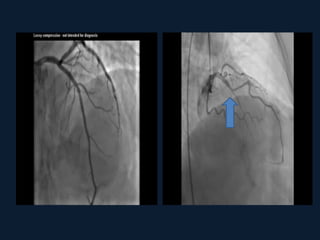

Typical systolic compression (arrows) of the mid

LAD at two sites in series.

Typical systolic compression(arrows) of the mid LAD at two sites in series.